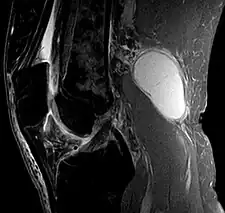

Baker's cyst on MRI, sagittal image -

Baker's cyst on MRI, sagittal image